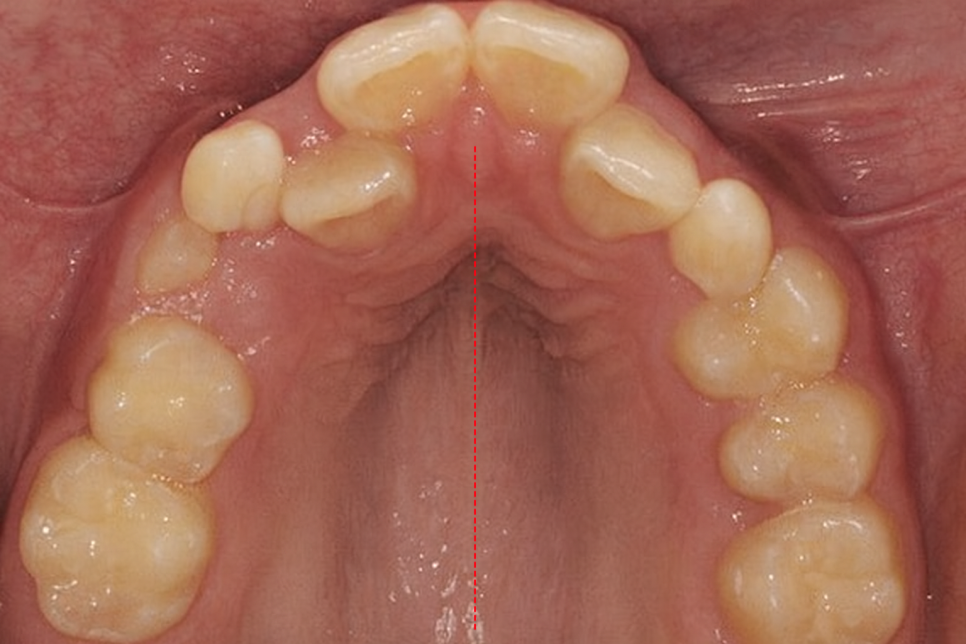

악궁 확장이 필요한 케이스.

내발산 치과 에서 준비한 사진처럼

공간이 좁아 영구치가 틀어져 올라오거나

올라오기 어렵다 판단되는 경우,

윗턱 뼈 자체를 넓혀주는 악궁 확장이

필요할 수 있습니다.

사진처럼 윗턱 뼈가 작아 치아가 겹쳐서 올라오는 케이스,

넓혀주는 과정이 필요하다 판단될 수 있습니다.